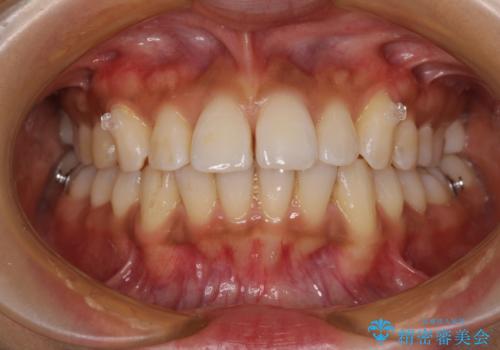

- 全体的な歯列の叢生を気にして来院された患者様です。

奥歯の咬み合わせを見ると、片方は上顎が下顎に対して相対的に前方にある状態でした。

咬み合わせを改善するためには、上顎臼歯を後方に移動させた咬み合わせにする必要があります。

インビザライン単体で改善することも可能ですが、ディープバイトのためインビザライン単体で達成する可能性が低いと考えられたため、カリエール・ディスタライザーという補助装置を併用して、より確実性を上げることとしました。

奥歯の咬み合わせ改善後に、インビザラインにて歯列を整えることとしました。

カリエールディスタライザーを併用したことで、確実かつ短期間で治療を終えることができました。